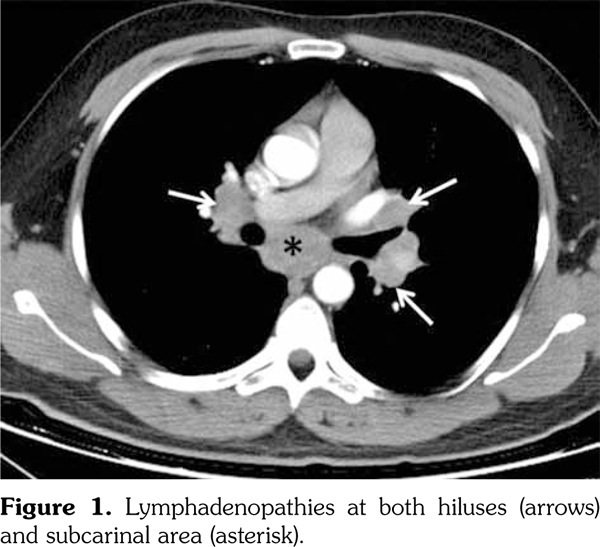

A 29-year-old male patient who had AS for 13 years applied to our rheumatology outpatient clinic for routine yearly control. His AS had been under control with etanercept for 43 months. After the routine follow-up evaluation, a thorax computed tomography scan was performed because of hilar enlargement in the chest X-ray. Multiple lymphadenopathies, the largest one with 2 cm in diameter, were detected in computed tomography scan (Figure 1).

Lymph node biopsy was performed by broncoscopy and endobronchial ultrasonography. Biopsy result was compatible with granulomatous disease. All the infectious studies performed on pulmonary lymph node tissues were negative. Angiotensin converting enzyme level was at the upper limit with a value of 47.6 U/L (normal: 8-52 U/L). Sarcoidosis was found to be compatible with the condition after excluding tuberculosis. Etanercept was ceased following the diagnosis of sarcoidosis. No additional medical treatment was suggested for sarcoidosis. Non- steroid anti-inflammatory drugs were prescribed for the control of AS. Five months later, follow- up thorax computed tomography scan showed resolution of the mediastinal lymphadenopathies (Figure 2).